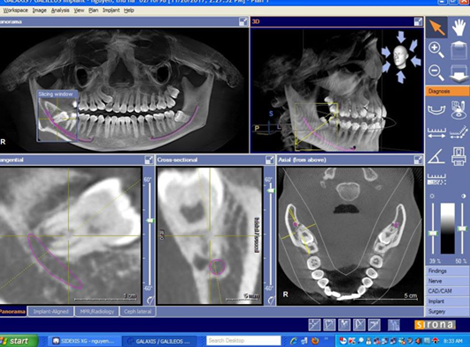

| - CBCT trong việc lập kế hoạch điều trị Implant sử dụng hình ảnh 3D và đa lớp cắt để xác định chính xác chiều cao, độ rộng và giải phẫu của phần xương hàm và xương ổ răng cũng như mối tương quan vùng mất răng với cấu trúc giải phẫu liền kề như ống thần kinh răng dưới. Đặt Implant với máng hướng dẫn phẫu thuật có thể được thực hiện với các dữ liệu CBCT. Với khả năng 3 chiều của CBCT, các nhà lâm sàng có thể quyết định liệu có cần đến việc ghép xương, nâng xoang trước khi đặt Implant hay không cũng như chọn kích thước implant phù hợp nhất cho từng vùng xương. | | |